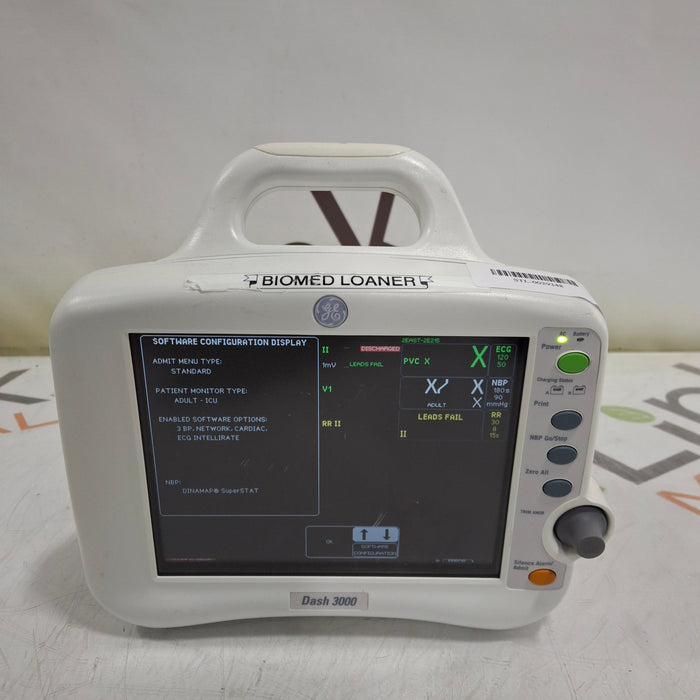

GE Healthcare Dash 3000 - GE/Nellcor SpO2 Patient Monitor

OEM: GE Healthcare

Material: Dash 3000 - GE/Nellcor SpO2

Common Name: Patient Monitor

Manufactured Date: 2005-12-01

Item Weight: 9.8

Serial Number: SBG05494209GA

SKU#: Inv-00502567

Powers On: Yes

Includes Power Cords: Yes

Functional Condition: Untested

Cosmetic Condition: Poor

Location: Hazelwood, MO 63042-2446

Notes: Device has multiple scratches on the screen